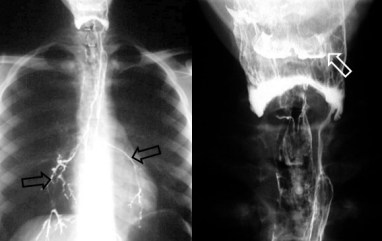

La retención de bario en los recesos faríngeos (valléculas) es signo de relajación incompleta o anormal del esfínter esofágico superior o de otro trastorno de la coordinación motora faringo-esofágica. En la imagen vemos el signo (flechas) en un paciente joven con un trastorno motor faringo-esofágico.

Obsérvese también el relleno en la radiografía de los senos piriformes (flecha blanca). La radiografía de tórax muestra el paso del bario al árbol traqueo-bronquial (flechas negras), prueba del trastorno deglutorio.